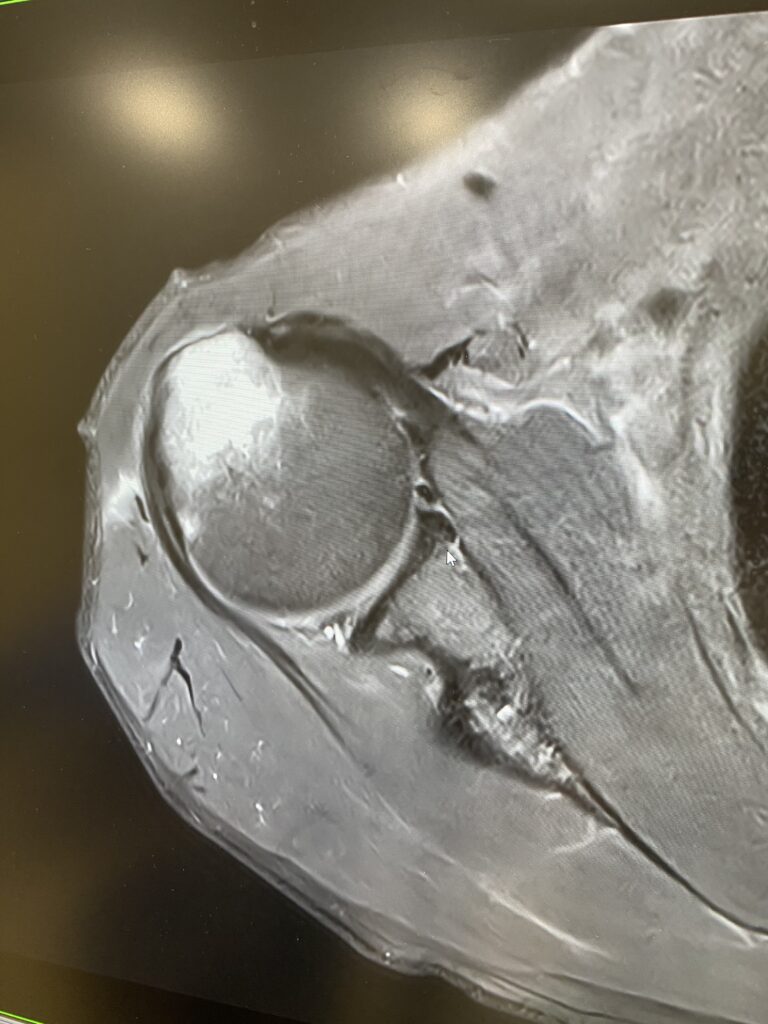

1.5T MRIへの更新作業が完了しました。

9月上旬から休止していたMRIの撮影が可能となり、画像精度が飛躍的に向上します。